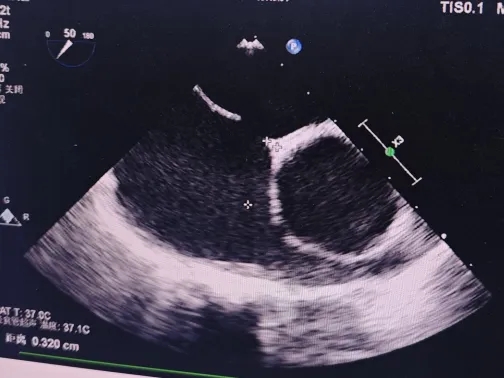

食道超声下缺损测量约14.7*11mm

食道超声下缺损主动脉侧残端约3mm

经食道超声描述:房间隔总长42mm,房间隔中部可见回声脱失约15mm,缺损距二尖瓣环约17mm,距离上腔静脉约9mm,主动脉侧残端约3mm。CDFI: 房水平见左向右分流信号。

术前食道超声可见房水平左向右分流